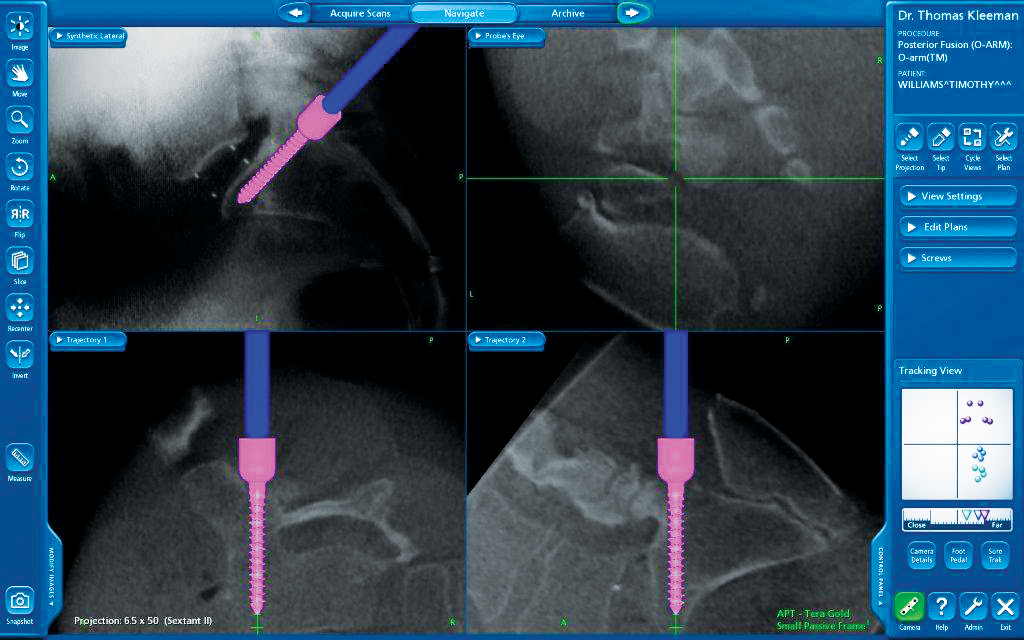

One of the most exciting new MIS techniques is the DLIF or "Direct Lateral Interbody Fusion". This technique requires a small 1" incision along the side of the abdomen allowing a bloodless approach to all levels of the lumbar spine except the lowest level L5-S1. Through this single incision it is often possible to correct complex multilevel deformity such as scoliosis.

L5-S1 is blocked from this direct lateral approach by the pelvis and since it is often involved in the pathology requiring a spinal fusion, a small innovative group of surgeons from around the country (including Dr. Thomas J. Kleeman from the New Hampshire Neurospine Institute) have been working together to solve this dilemma to allow L5-S1 to be accessed in a manner similar to the DLIF. This novel technique has been called the OLIF or "oblique lumbar interbody fusion". The OLIF is done "obliquely" (in front of the iliac crest) which gives direct access to L5-S1 while avoiding the back muscles (posterior fusion) and abdominal structures (anterior fusion). This approach allows us to use a single larger implant providing a larger fusion area and greater stability. Thus far, most of the patients were allowed to leave the hospital within 24 hours of their surgery. As with all procedures performed at NHNSI, we continually review the benefits and indications of this approach. We strive to provide the most effective and least invasive approaches to spine surgery. Our varied specialists provide us with a vast knowledge of techniques so we can bring you, the patient, the best solutions for your condition.